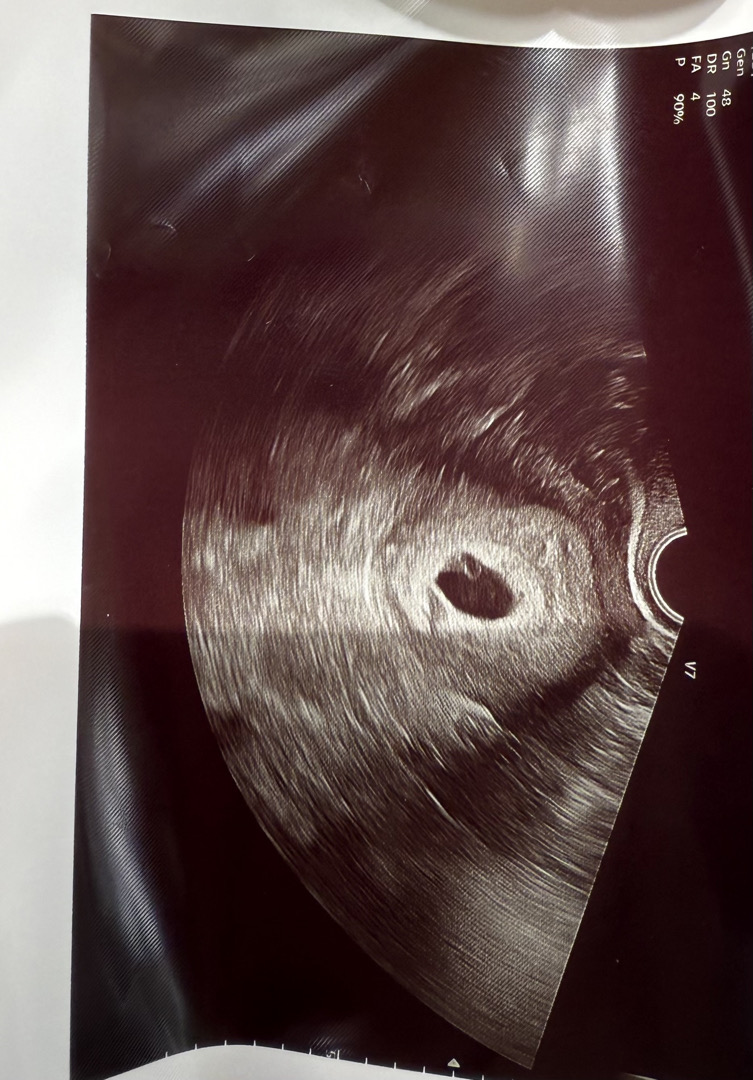

직장 앞 병원과 집 앞 병원을 왔다갔다 하는 편이예요. 이번주 월요일에 직장 앞 병원 갔다가 난황이랑 아기집 예쁘게 잘 보고왔다고 걱정없다고 해서 안심했어요! 피고임도 없고 건강하다구요 근데 오늘 집 앞 병원 가니 초음파 모양이 동그랗지 않아서 잘 모르겠다고 하시고,, 난황은 보이는데 잘 안보인다고 하시더라구요..ㅠ 근데 누가봐도 회사 앞 산부인과 기계가 더 선명하고 잘보여요. 어떤걸 믿어야하나요? 사진은 직장앞에서 받아온 사진입니다!